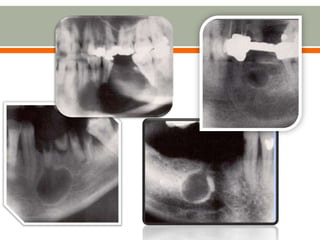

 Round/ovoid radiolucency with an opaque border

 Apex of the tooth is within the radiolucency

 Adjacent teeth and structures are displaced

 Infected cyst:

o Poorly demarcated borders

o Background structures become invisible and the defect appears

as tunneling

o PDL space around the involved tooth becomes widened

 Round/ovoid radiolucencywith an opaque border  Apex of the tooth is within the radiolucency  Adjacent teeth and structures are displaced  Infected cyst: o Poorly demarcated borders o Background structures become invisible and the defect appears as tunneling o PDL space around the involved tooth becomes widened